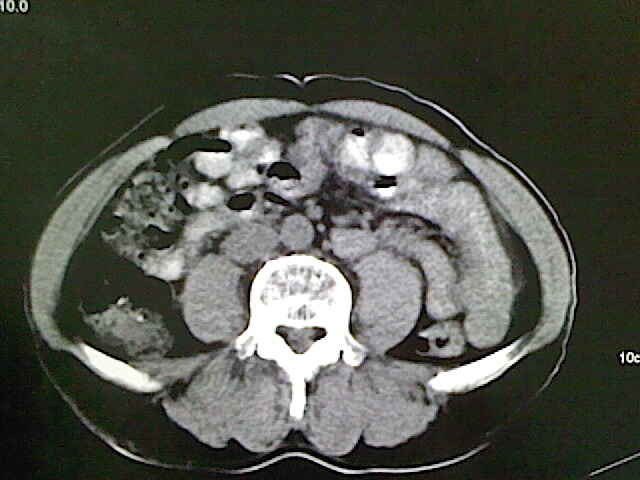

标题: CT18630:男,54岁,乙肝,大家看怎么样? [打印本页]

男,54岁,乙肝,大家看怎么样?

肝脏的要有增强敢说话

未见明确异常;建议必要时行ct增强扫描检查。